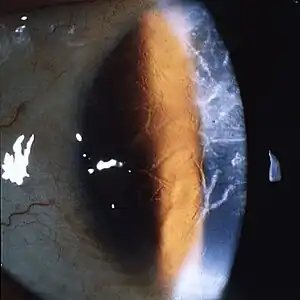

| A network of thick linear corneal opacities in patient with a variant of LCD1 (LCD type III) due to a homozygous p. Leu527Arg mutation in the TGFBI gene | |

Filamentous opacities appear in the cornea with intertwining delicate branching processes. During an eye examination, the doctor sees these deposits in the stroma as clear, comma-shaped overlapping dots and branching filaments, creating a lattice effect. Over time, the lattice lines will grow opaque and involve more of the stroma. They will also gradually converge, giving the cornea a cloudiness that may also reduce vision. The disease is bilateral, usually noted before the end of the first decade of life. Although lattice dystrophy can occur at any time in life, the condition usually arises in children between the ages of two and seven.

In the examination of biomicroscopy, it appears as branches spread on the corneal stroma in the appearance of ghost vessels. diagnosis can also be confirmed with anterior segment OCT (Visante OCT, spectral domain OCT).The interwoven linear opaque filaments have some resemblance to NERVES, but may not be observed in all affected members of families with the condition. Recurrent corneal erosions may precede the corneal opacities and even appear in individuals lacking recognizable stromal disease. Amyloid deposits are found throughout the corneal stroma. Linear and other shaped opaque areas accumulate particularly within the central corneal stroma, while the peripheral cornea remains relatively transparent.